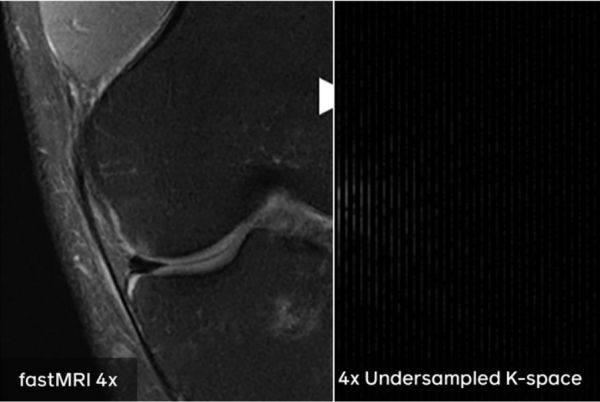

目前,这种技术可以达到,让AI从收集到的四分之一的原始数据中,自己创建完整的图像。也就是说,如果完整的检查需要20分钟,那么利用这个技术,病人只需要躺着仪器中5分钟,fastMRI 就可以通过这五分钟收集到的数据,自己创建出一个完整的图像。这比传统的 MRI 快了四倍。

为了创建需要审查的图像,MRI使用磁场与身体软组织和重要器官中的氢原子相互作用。这些原子然后发出电磁信号,就像灯塔一样,指示原子在身体的什么位置。这些信号被扫描仪收集为一连串单独的二维频率测量,即所谓的k空间数据。

一旦所有数据最终收集完毕,系统就会将一个复杂的数学公式—逆傅里叶变换—应用到该原始k空间数据中,以创建膝关节、背部或大脑或身体其他区域的详细MR图像。如果没有一套完整的数据点,数学无法准确地指出每个信号的来源。

fastMRI团队使用了一种完全不同的方式来创建图像,这种方式需要的原始数据要少得多。研究人员建立了一个神经网络,并使用世界上最大的膝关节MRI开源数据集对其进行训练,该数据集由纽约大学Langone Health创建和共享,并作为fastMRI计划的一部分。

fastMRI研究团队删除了每次扫描中大约四分之三的原始数据,然后将剩余的信息输入到AI模型中。然后,该模型学会了从有限的数据中生成完整的图像。重要的是,AI生成的图像并不只是看起来像普通的MRI,它生成的图像与标准的MRI过程创建的地面真实图像相匹配。